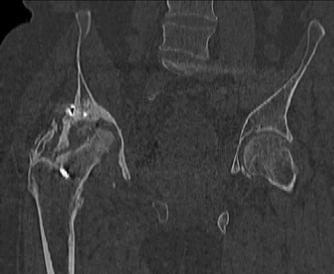

Пациент 49 лет, паровозная травма 23.2.2006, получил вертикальная нестабильное повреждение таза, разрыв левого крестцово-подвздошного сочленения, перелом лонной, седалищной костей слева, T-образный оскольчатый перелом правой вертлужной впадины с переломом заднего края, вывих правого бедра, посттравматическая пояснично-крестцовая плексопатия с обеих сторон, паралич мышц правой голени.

В день травмы - вправление вывиха, скелетное вытяжение, 14.3.2006 чрескостный остеосинтез таза. 20.4.2006 остеосинтез правой вертлужной впадины пластинами, осложнившийся нагноением межмышечной гематомы правой ягодичной области. Получал консервативное лечение, было достигнуто полное заживление раны. 24.7.2006 введены илиосакральные винты слева. С декабря 2006 года и по настоящее время ходит на костылях без опоры на правую ногу. Планируется THA. Помогите определиться с вариантом костной пластики? И какую укрепляющую конструкцию использовать?